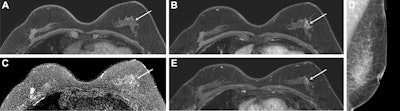

Images show a 57-year-old woman who had contralateral breast tumor recurrence detected at abbreviated MRI 30 months after breast-conserving surgery. (A) Precontrast and (B) postcontrast T1-weighted MRI scans show a 1.6-cm focal heterogeneous non-mass enhancement (arrow) in the left upper outer breast. (C) Axial T2-weighted MRI scan shows no abnormal findings at the corresponding site (arrow). MRI-guided biopsy revealed low-grade DCIS. (D) Left mediolateral oblique mammogram six months before MRI shows no abnormal findings. (E) On retrospective review, there was a small non-mass enhancement (arrow) at MRI one year prior, but it was interpreted as a benign finding by a radiologist at that time. The lesion was finally proven to be invasive ductal carcinoma in the background of DCIS at the surgical histopathologic examination. Images courtesy of the RSNA.For women with a personal history of breast cancer, there is no consensus among researchers on the best use of MRI screening. Previous retrospective research has shown that an abbreviated MRI protocol can detect breast cancers at a higher rate compared to digital breast tomosynthesis (DBT) in women with dense breasts, as well as comparable performances to full-protocol MRI.